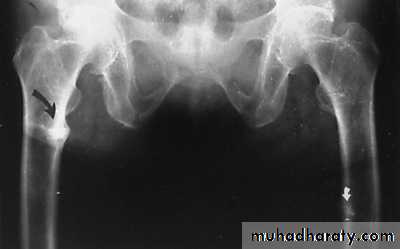

In rickets the changes are maximal where bone growth is occurring , so they are best seen at the knee, wrist and ankle .seen as

. Deficient the zone of provisional calcification .

.widening with irregularly mineralized metaphyses with cupping

.increase distance between the visible epiphysis & the calcified portion of the metaphysis .

.generalized decrease in bone density .

. Deformities of the bones occur because the under mineralized bone is soft , green stick fractures are common .